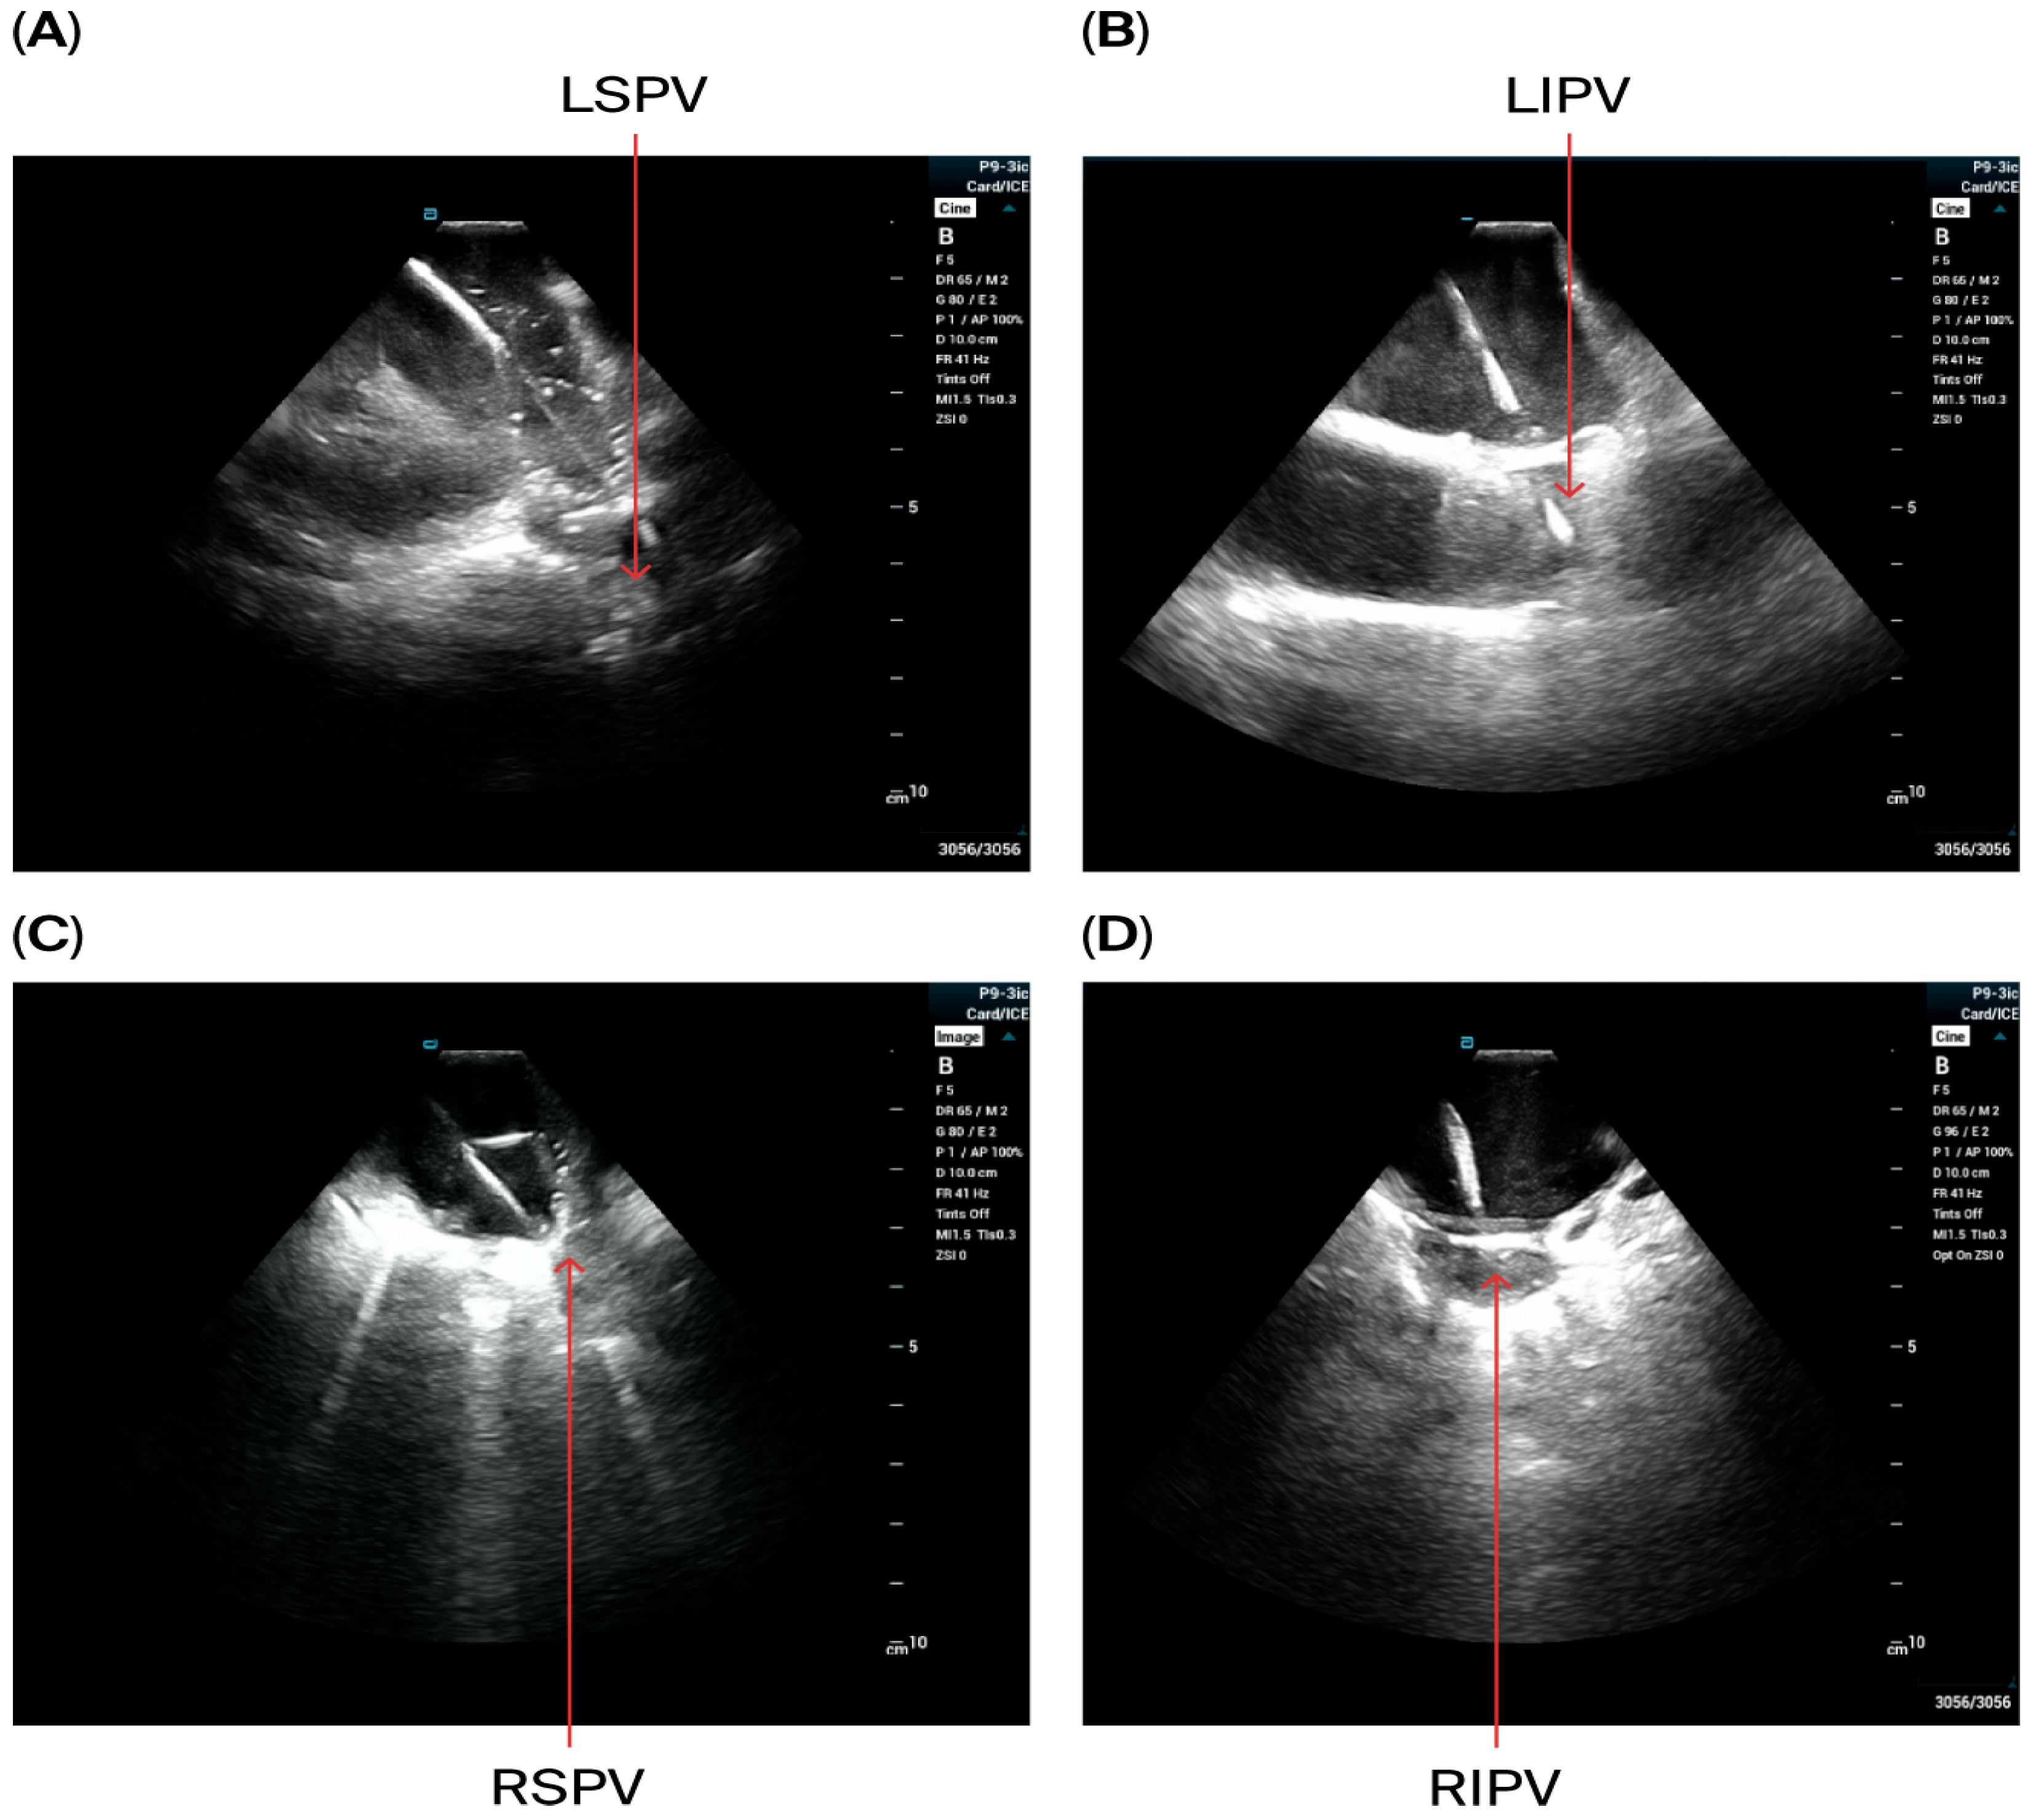

- A circular mapping catheter (CMC) or high-density catheter (with repeated ablation) was advanced to the LA via the Faradrive sheath. Electroanatomic mapping of the LA, including detailed voltage assessment was performed. Then, over the J-tip wire, the Farawave pentaspline catheter was advanced to the LA via the Faradrive sheath. The 0.035-inch J-tip guidewire was attached to the EnSite mapping system’s pin box via a DuoMode extension cable (Boston Scientific, Marlborough, MA, USA) for additional visualization in LA and pulmonary veins. ICE catheter imaging was used to ensure appropriate catheter positioning and catheter–tissue contact with each PV and LAPW PFA lesion delivered. Prior to ablation, 0.2 mg of intravenous glycopyrrolate was administered to all patients to avoid vagal reactions during PVI.

- PV isolation was performed with the PFA catheter placed at the PV ostium, with 4 applications in the basket configuration and 4 in the flower configuration for a total of 8 applications per PV. Appropriate rotation of the catheter following 2 applications in each position was assured with LA ICE and EAM visualization. Two additional applications in the flower configuration were delivered at the operator’s discretion in the left and right carina, towards the LA ridge and septal aspect of the right pulmonary veins based on the anatomy and presence of atrial potentials.

- LAPW isolation was achieved with overlapping lesions placed in the flower configuration, with 2 application per site. With the J-tip wire in the left PV serving as a ‘hook’, rotating the catheter clockwise in the flower configuration allowed ablation of the posterior wall near the left veins; similarly, with the J-tip wire in the right pulmonary veins, rotating the catheter counterclockwise allowed appropriate contact for the posterior wall isolation near right veins. Remaining mid-posterior wall was ablated with overlying lesions in the flower configuration. ICE was used with each ablation application to ensure optimal contact.

- Cardioversion was performed if the patient remained in atrial fibrillation post-ablation. PV isolation was confirmed by the presence of entrance and exit blocks in all PVs, while posterior wall isolation was determined by the complete abolishment of posterior wall potentials from the LA roof to just below the lower regions of the inferior PVs.